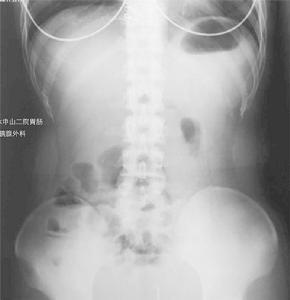

X光片病因尚未明,可能为多种致病因素的综合作用,与免疫异常、感染和遗传因素似较有关。

肠道钡餐造影能了解末端回肠或其他小肠的病变和范围。其表现有胃肠道的炎性病变,如裂隙状溃疡、卵石征、假息肉、单发或多发性狭窄、痰管形成等,病变呈节段性分布。钡剂灌肠有助于结肠病变的诊断,气钡双重造影可提高诊断率。X线腹部平片可见肠拌扩张和肠外块影。腹部CT,检查对确定是否有增厚且相互分隔的肠袢,而且与腹腔内脓肿进行鉴别诊断有一定价值。